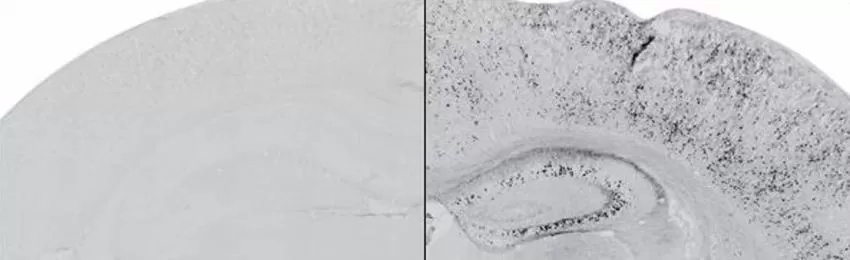

Investigadores del grupo 'Disfunción sináptica y enfermedad' del Instituto de Biomedicina de Sevilla (IBIS), liderado por los doctores Francisco Gómez Scholl y Amalia Martínez Mir, en colaboración con el grupo de la División de Neurociencias de la Universidad Pablo de Olavide (UPO), dirigido por el doctor José María Delgado García, han publicado un estudio sobre el Alzheimer cuyos datos sugieren que la acumulación de un fragmento de la proteína sináptica neurexina en el cerebro adulto de un modelo animal de ratón provoca pérdidas concretas de memoria.

Según han detallado ambas instituciones a través de un comunicado, la aportación supone un paso previo al estudio de la proteína en muestras de pacientes con la finalidad de prevenir su acumulación y, como consecuencia, los síntomas asociados. Los datos experimentales han sido obtenidos a partir de un modelo animal de ratón generado por los investigadores que reproduce la acumulación del fragmento proteico durante la enfermedad.

Los investigadores se han centrado en el estudio de un fragmento de la proteína sináptica neurexina, denominada en el ámbito científico como NrxnCTF. Este fragmento se acumula en los casos de mutación en los genes de presenilinas responsables de formas familiares de Alzheimer.

Los expertos han observado que su acumulación experimental en el cerebro adulto del modelo animal desencadena defectos específicos de memoria, entre otros. Estos modelos experimentales de enfermedad son importantes para la identificación de mecanismos patogénicos y fundamentales para el diseño de terapias efectivas.

Los científicos observan en estudios de comportamiento que la acumulación de dicha proteína produce una pérdida de memoria asociativa que depende de la amígdala del cerebro. En colaboración con el doctor José María Delgado se han estudiado las conexiones sinápticas de la corteza prefrontal a la amígdala mediante registros electrofisiológicos en ratones. Estos experimentos han mostrado que la acumulación de NrxnCTF produce también defectos en la plasticidad presináptica.